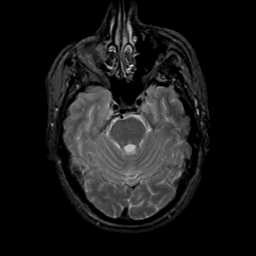

MR Study #18, July 21, 1991 -- Slice #15